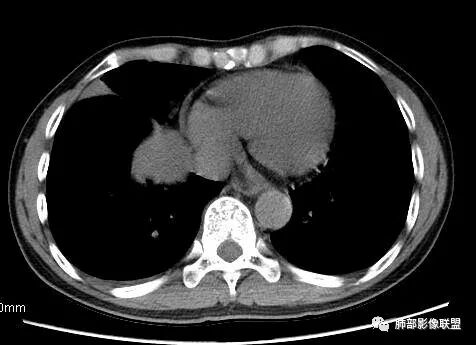

南边:这类片其实很艰难Shelia:应该有个增强崇军:是的,如果没有老师您以前的讲述,一个肺门占位就发出去了风儿:肿块跨叶生长,边缘光滑,有膨隆有平直,支气管血管受压,病灶后方支气管似乎进入病灶后堵塞,与纵隔胸膜呈锐角,来源肺内-神经内分泌肿瘤?胸膜-SFT?血管-PSP?临近心包少量积液右侧胸腔少量积液是否与肿块有关

南边:从叶裂的变形,下朝上,越来越朝前扭曲,提示叶裂局部有朝前上推移的趋势

5.病灶密度大多不均,不规则坏死液化,少数病例出现钙化。增强扫描常观察到由外而内的厚壁不均匀强化,中央半岛样强化等等,厚壁中或实性区常能显示血管影。一些病灶中央呈现边界清楚囊样变。

6.病灶侵犯胸膜时可以出现胸水,病灶可以侵犯胸壁并引起相应临床症状。